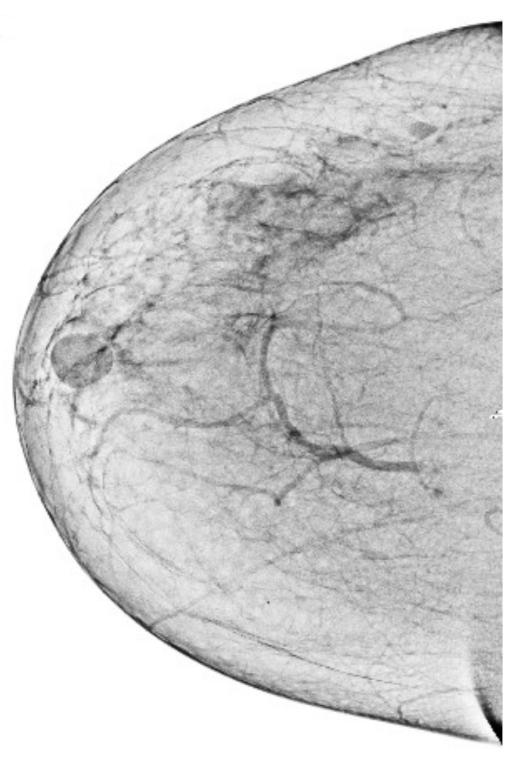

Figure 5.

Final breast image after removal of pectoral muscle.

After getting a grayscale image, the next step is to reduce the pectoral muscle, as shown in Figure 5. We used the seed-based region growth technique to shrink the pectoral muscle to get the breast part. The breast is the region of interest in the mammogram images, and the breast contains the cancerous region. The seed region growing is one method of image segmentation, and it contains two operating principles. One principle is based on selecting the pixel location value and the other principle is selecting the seed point. We used the seed point method because it automatically gives an accurate selection based on the orientation of the image. In our case, the seed point is automatically selected considering the orientation of the mammographic image. The seed points are obtained by using the neighboring pixels of the seed and determining whether subsequent pixels should be added to the region or not. This process is continuous and iterative until the segmentation of the region of interest. The output of the seed region growing technique is shown in the Figure 5, and the breast region is observed to be affected. It facilitates obtaining abnormal region or cancerous region for segmentation of abnormal region, which leads to the higher classification accuracy of breast cancer detection. It is briefly explained in the Section 5.